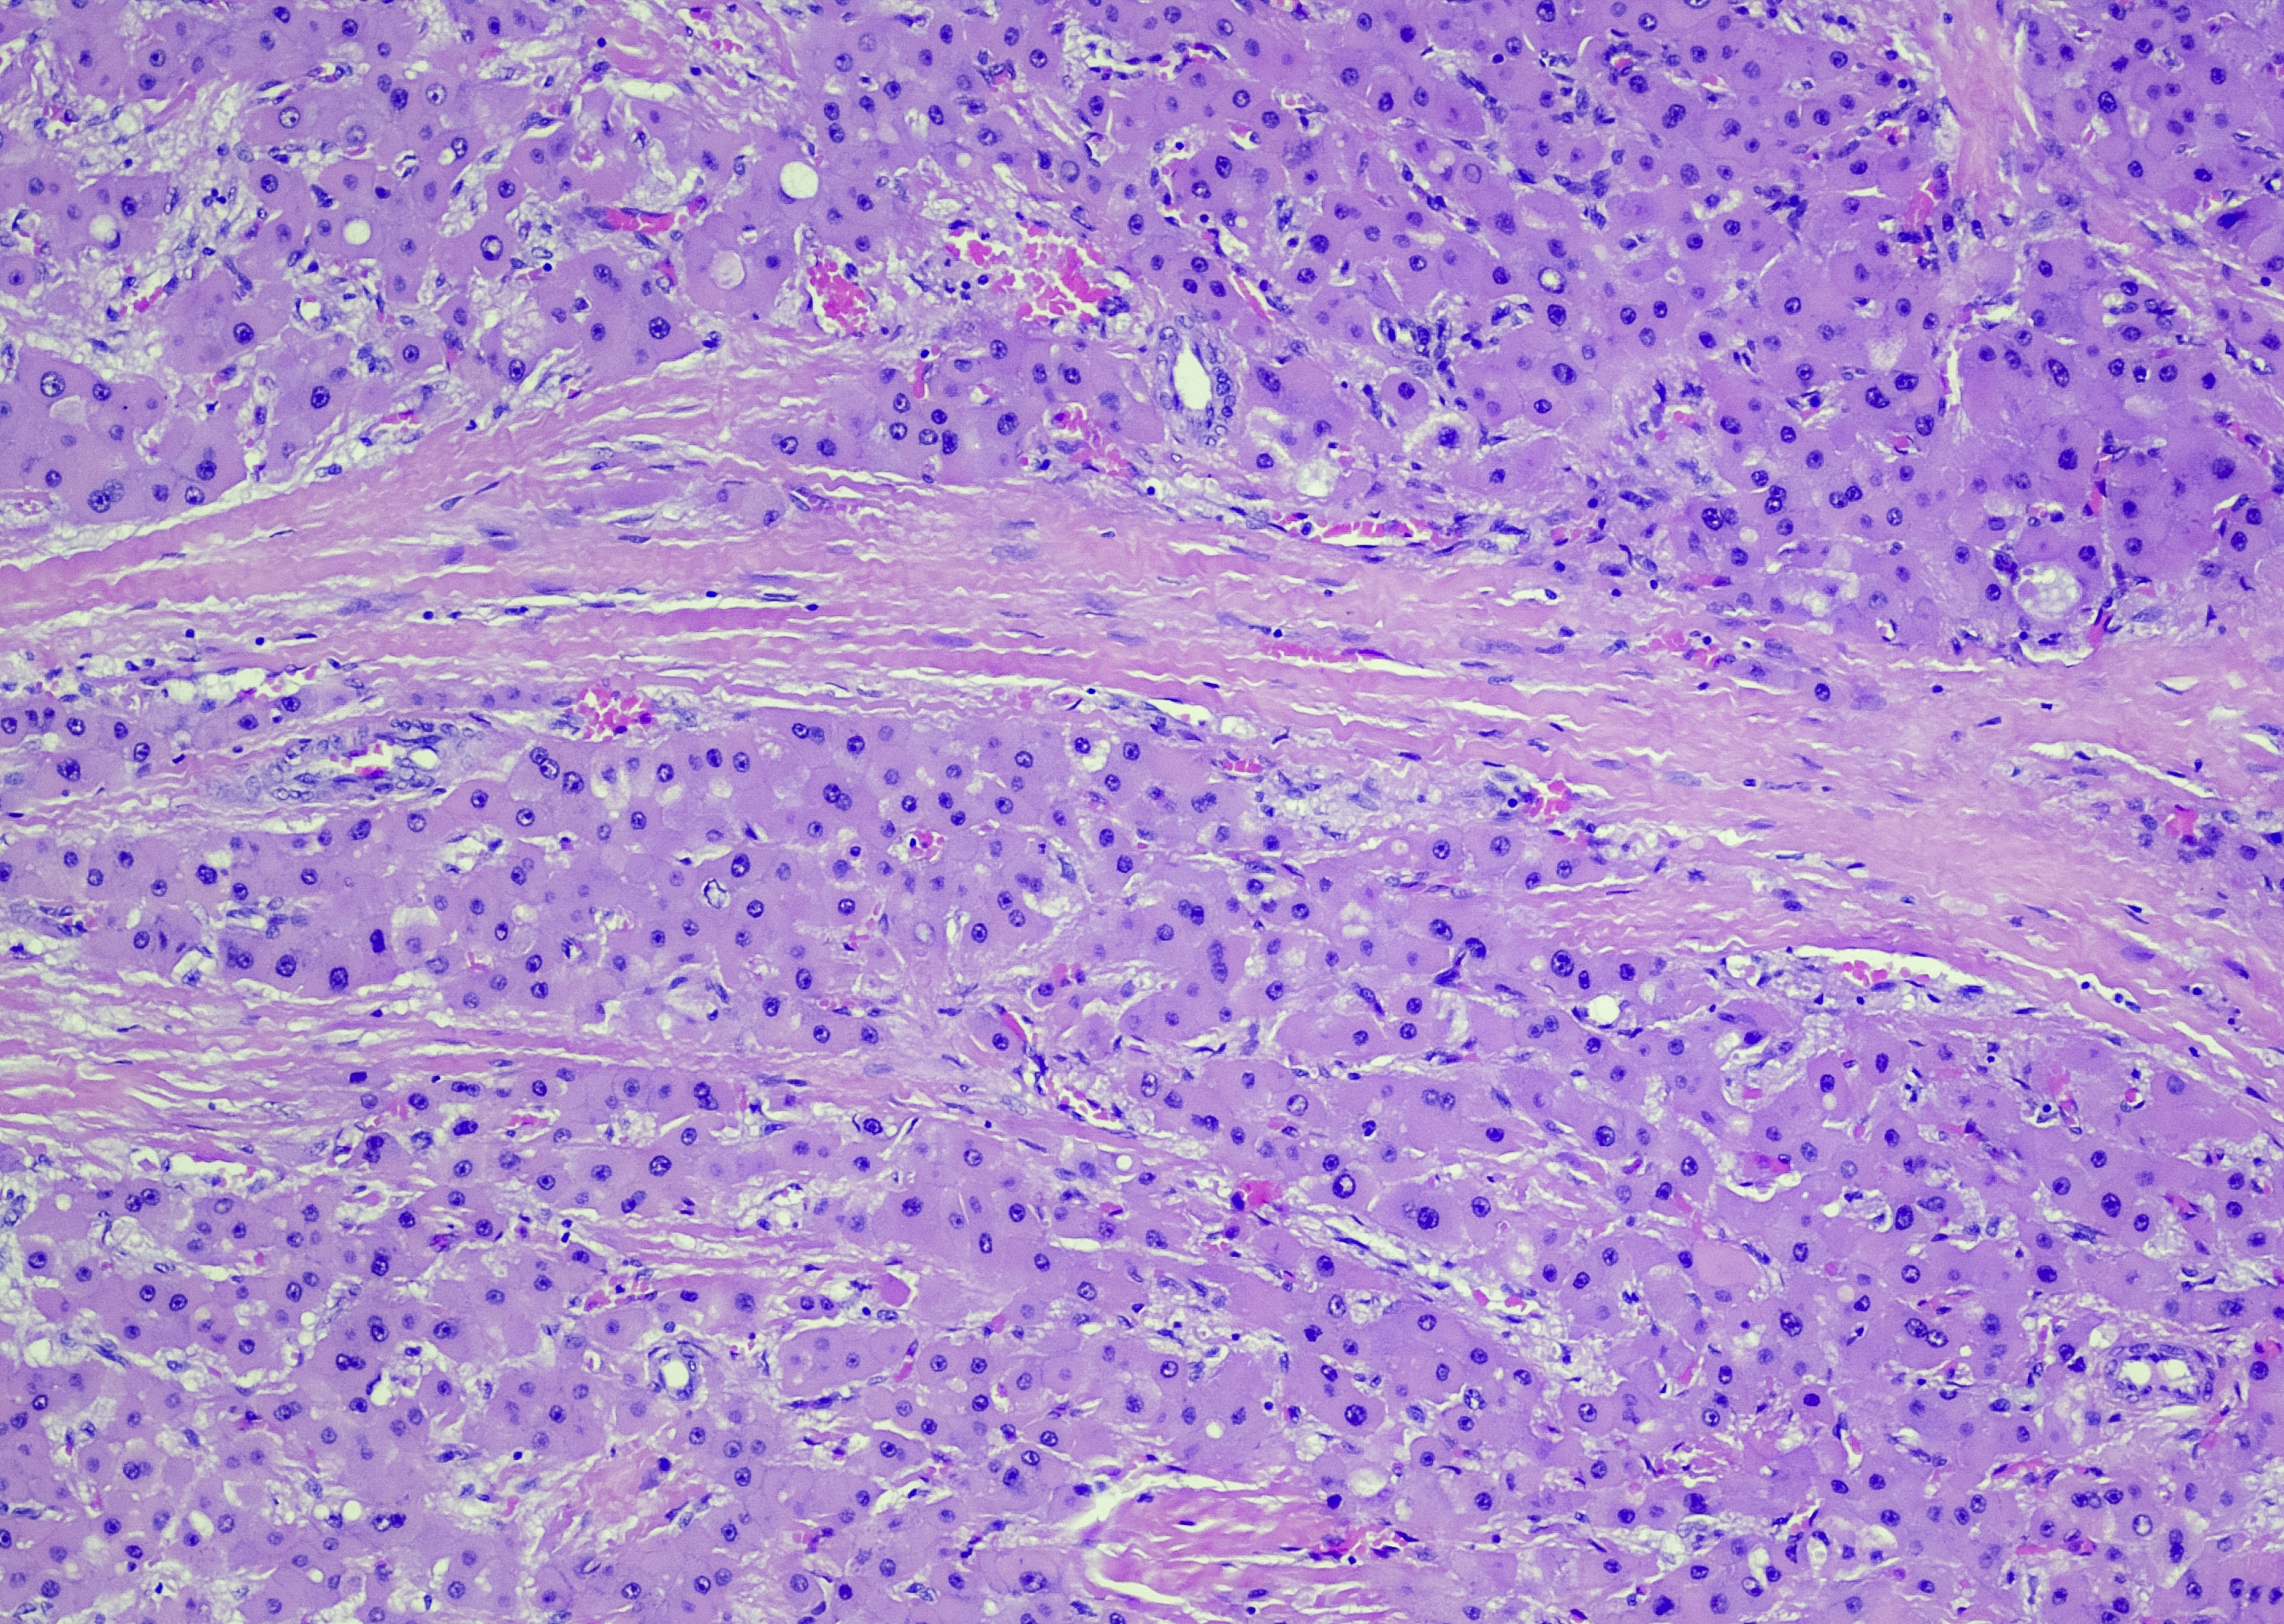

Primary liver cancers, which are rarer in Western countries, begin in the liver. Hepatocellular carcinoma is the most common type.

Hepatocellular Carcinoma (HCC) is usually often in people with pre-existing liver disease or conditions and is often aggressive. Other less common liver cancer types such as Cholangiocarcinoma or Angiosarcoma, can sometimes be less.